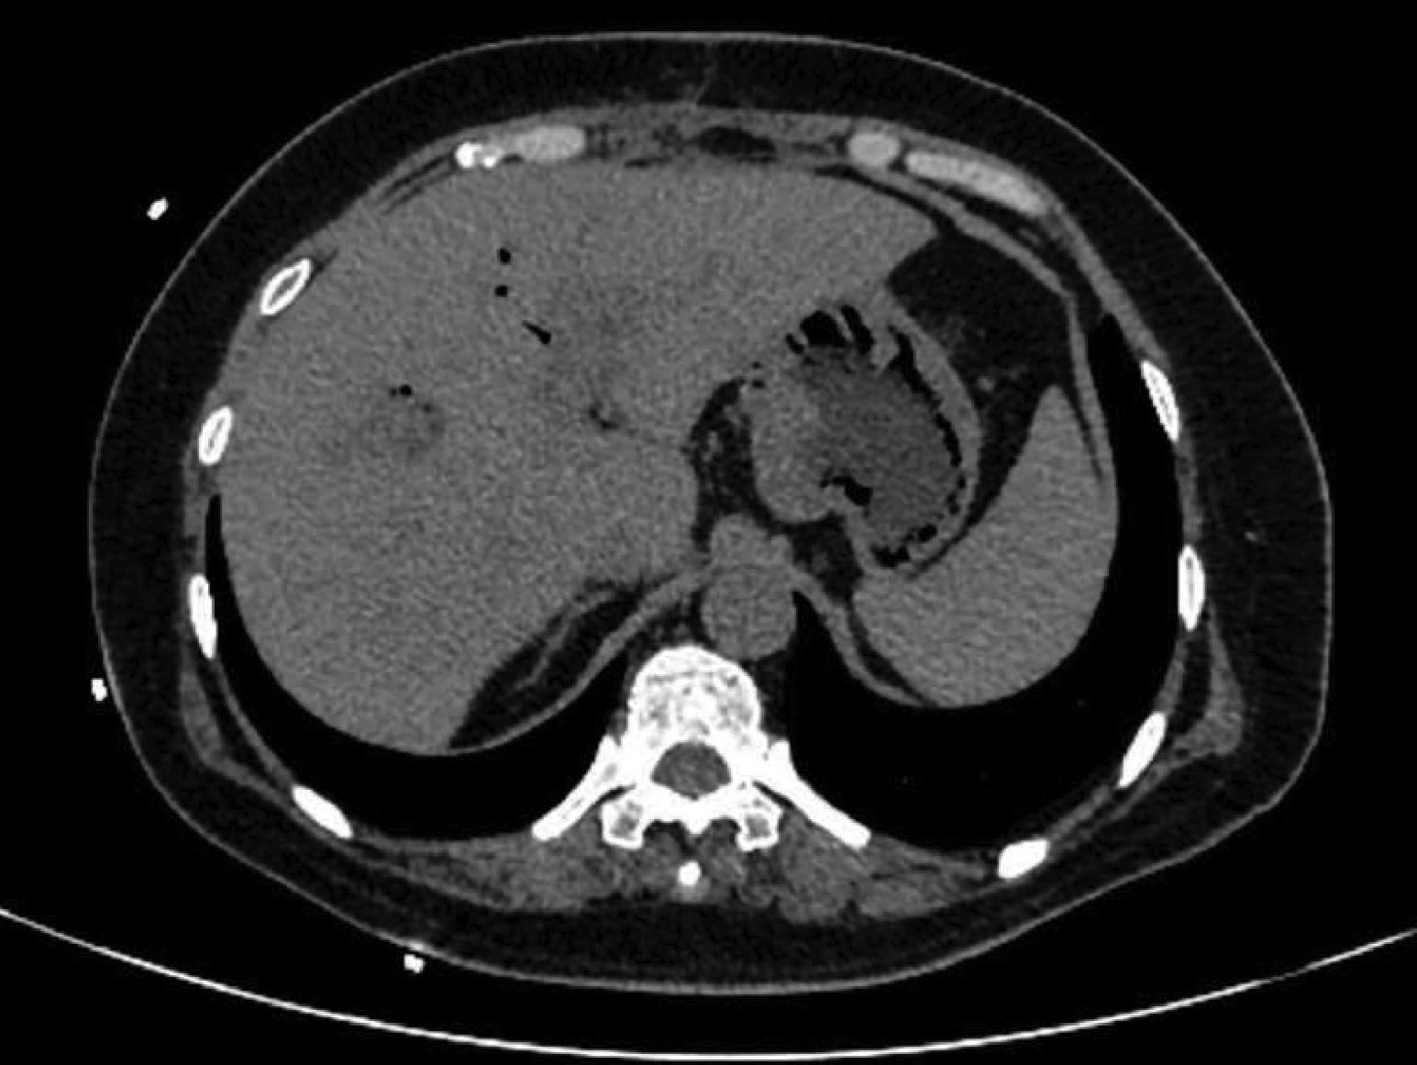

目的  本研究旨在寻找乙型肝炎肝硬化CT特征,建立肝硬化上消化道出血预测模型,预测出血风险。  方法  回顾性分析2015年1月—2021年6月天津市第一中心医院101例型肝炎肝硬化患者的数据,将其分为上消化道出血组(P=58)及非出血组(n=43)。比较两组间实验室检查以及强化CT检查测的平扫期、动脉期、门脉期以及静脉期的CT值,并计算各期间CT值的变化(ΔCT)。计量资料两组间的比较使用t检验或Mann-Whitney U检验;使用logistic回归分析方法,预测相关危险因素;通过计算受试者工作特征曲线下的面积评估模型辨别力,而模型校准则通过Hosmer-Lemeshow确定。在多变量logistic回归分析结果的基础上,使用Rstudio4.1.2软件的R包构建预测的列线图模型,并绘制相应的ROC曲线、校准曲线以及临床决策曲线。  结果  非出血组血清TBil、WBC、PLT水平与出血组比较,差异均有统计学意义(P值均<0.05);两组在肝-Plain、脾-P-Plain、脾-P-A ΔCT值存在统计学差异(P值均<0.05)。单因素logistic分析结果显示,白细胞(OR=0.770,95%CI:0.624~0952, P=0.016)、血小板(OR=0.979,95%CI:0.965~0.994, P=0.006)、肝脏平扫期(OR=1.142,95%CI:1.058~1.233, P=0.001)、脾脏门脉期-平扫ΔCT值(OR=0.979,95%CI:0.959~1.000, P=0.050)、脾脏门脉期-动脉期ΔCT值(OR=0.979,95%CI:0.944~0.994, P=0.015)在乙型肝炎肝硬化患者发生上消化道出血与未出血两者之间差异具有统计学意义。多因素logistic分析结果显示血小板(OR=0.968,95%CI:0.944~0.993, P=0.011)、肝脏平扫期(OR=1.148,95%CI:1.047~1.259, P=0.003)、脾脏门脉期-动脉期ΔCT值(OR=0.951,95%CI:0.908~0.995, P=0.030)为上消化道出血的独立危险因素。基于多因素logistic分析结果,构建了乙型肝炎肝硬化上消化道出血的预测模型并绘制校准曲线。该模型的受试者特征曲线下面积为0.801,cut-off值为0.433,其对应的敏感度是81.4%,特异度是77.6%。模型的校准曲线与理想曲线贴合良好。  结论  乙型肝炎肝硬化肝脏具有特殊的ΔCT变化,通过ΔCT构建的预测模型对于乙型肝炎肝硬化上消化道出血具有良好的预测能力。